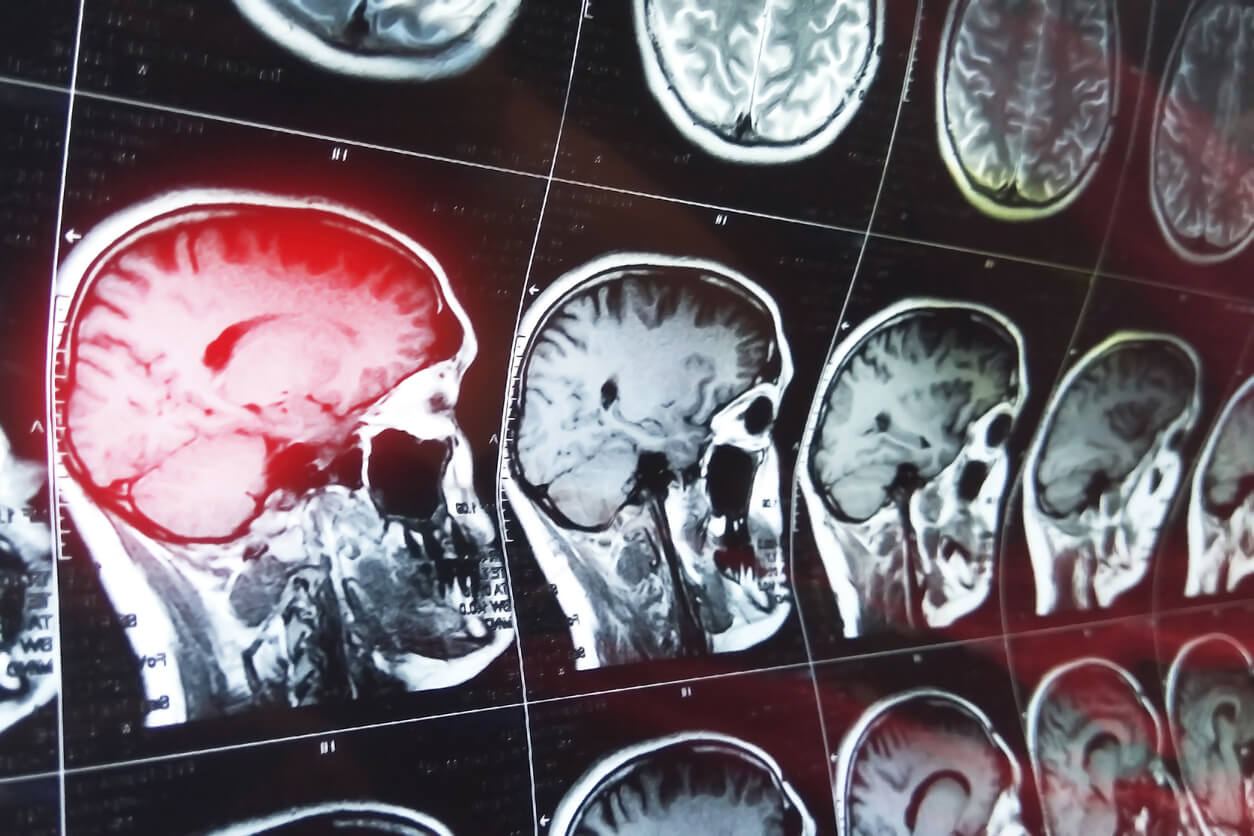

A stroke, also known as a cerebrovascular accident (CVA), is a critical medical event where the brain's blood supply is interrupted, leading to brain cell damage or death. Strokes fall into two primary categories: ischemic and hemorrhagic. An ischemic stroke occurs when a blood clot blocks a vessel, reducing blood flow to the brain, while a hemorrhagic stroke is caused by a burst vessel, leading to bleeding and increased pressure within the brain.